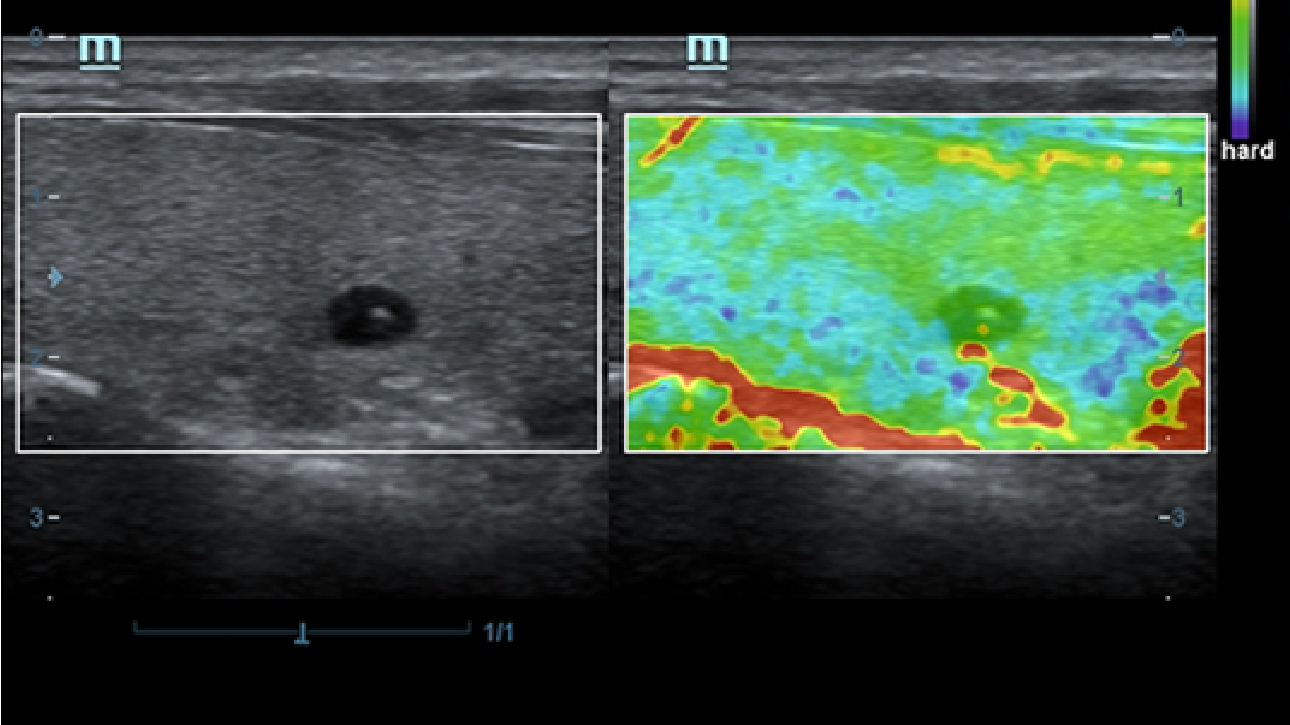

X-Insight es la soluci├│n intuitiva para una mejor visualizaci├│n.

La nueva soluci├│n de Mindray es una excelente transformaci├│n desde la continua comprensi├│n de las necesidades cl├Łnicas del usuario, combinada con la evoluci├│n de la tecnolog├Ła de los ultrasonidos m├Īs puntera. Repleto de vitalidad, con el ├║nico objetivo de visualizar el futuro y evitar los l├Łmites, el ec├│grafo DC-60Exp con X-Insight est├Ī constantemente mejorando con una escalabilidad aumentada. Como un socio personal, el equipo de ultrasonidos DC-60 Exp con X-Insight se centra en lo que verdaderamente importa, ayudando al usuario a administrar su pr├Īctica cl├Łnica con facilidad y seguridad.

Bas├Īndose en una profunda comprensi├│n de las necesidades del usuario, el sistema de ultrasonidos DC-60 Exp con X-Insight est├Ī dise?ado para ofrecer una alta eficiencia con im├Īgenes de precisi├│n, la cual se ve potenciada por una claridad inmediata, una inteligencia excepcional y benefici├Īndose de una c├│moda experiencia.